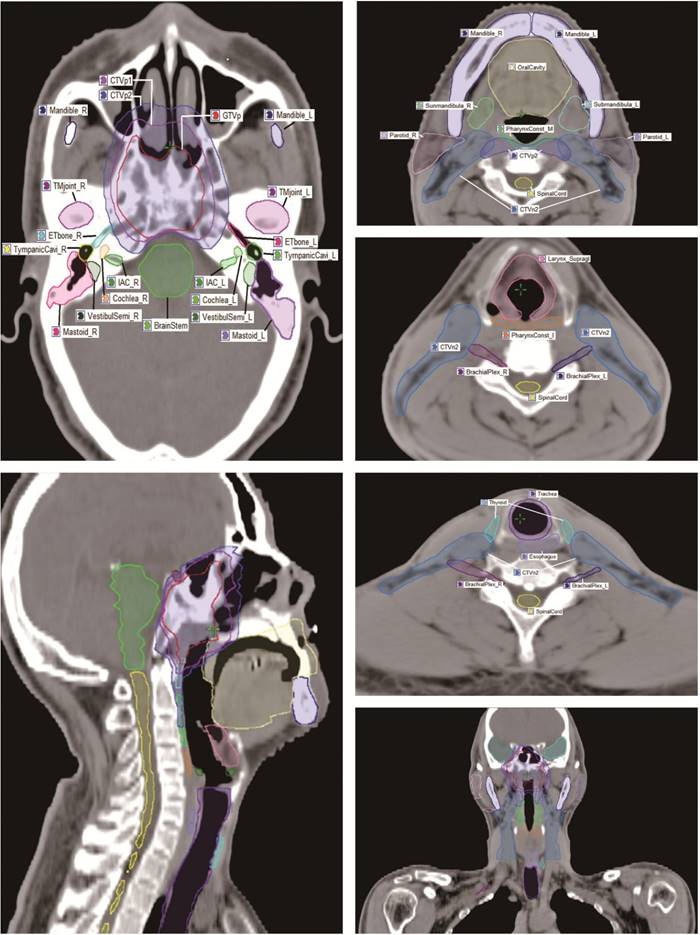

For the anatomic site specificity of NPC, the radiation field of traditional radiotherapy usually involved many normal tissues. In the present study, a total of 28 OARs surrounding the nasopharynx were analyzed, including the brain stem, optic nerve, spinal cord, temporal lobe, chiasm, pituitary, parotid, mandible, lens, eye, temporomandibular (TM) joint, oral cavity, cochlea, internal auditory canal (IAC), vestibule and semicircular canal (VestibulSemi), Eustachian tube, thyroid, trachea, esophagus, larynx, pharynx, brachial plexus, and et al. Based on the anatomic definition and pathogenesis of radiation induced injury, an experienced radiation oncologist manually contoured OARs on the planning CT scans of the 148 patients with a reasonable contouring method (Fig. 1) [10]. Critical organs, such as the brain stem and spinal cord, plus 3 mm margins were used to generate the planning organ-at-risk volume (PRV), and denoted as “BrainStem_PRV” and “SpinalCord_PRV”, respectively.

Figure 1

The contouring atlas of target volume and OARs surrounding nasopharynx.